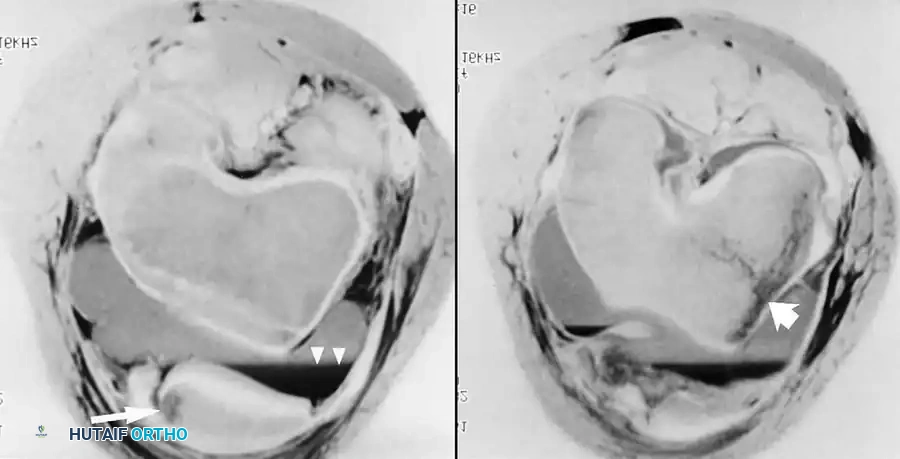

لا تقتصر قوة الرنين المغناطيسي على مفصل الورك فحسب، بل تمتد لتشمل المفاصل الأخرى كالركبة، مما يثبت فعالية هذه التقنية في كشف أدق التفاصيل التشريحية والمرضية في العظام والغضاريف. نستعرض هنا بعض الأمثلة التي توضح دقة الرنين المغناطيسي في تشخيص إصابات المفاصل:

هذه الصور تؤكد بما لا يدع مجالا للشك أن الاعتماد على الرنين المغناطيسي يوفر خريطة طريق واضحة للطبيب المعالج، سواء كان يتعامل مع كيس زلالي، أو كدمة عظمية، أو كسر خفي في صفيحة النمو، أو آفة غضروفية، مما ينعكس إيجابا على دقة التشخيص في مفصل الورك والمفاصل الأخرى.